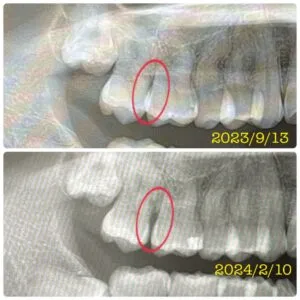

・写真4枚目の赤⭕️部分は、必要な歯のスペースが確保され、隙間ができている箇所